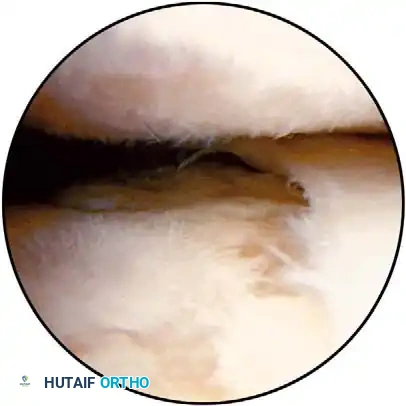

Early identification of micro-instability is paramount. Subtle instability often precipitates superior labral anterior and posterior (SLAP) lesions and secondary rotator cuff impingement. By identifying these lesions early, treatment can be directed at the root biomechanical cause rather than merely the secondary symptoms.

Clinical Pearl: The "Peel-Back" Mechanism

In the overhead throwing athlete, the shoulder is repeatedly placed in extreme abduction, hyperextension, and external rotation (the late cocking phase). This position forces the greater tuberosity and the undersurface of the rotator cuff to impinge against the posterosuperior glenoid rim and labrum. This internal impingement results in fraying of the cuff undersurface and the superior labrum. Repetitive microtrauma leads to anteroinferior ligamentous laxity and a "peel-back" of the posterosuperior capsular complex.